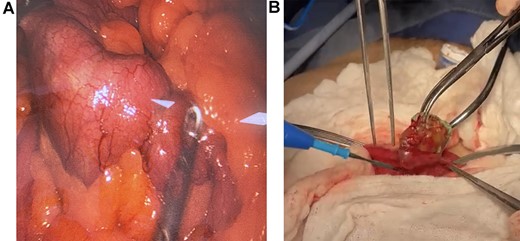

The abdominal CT revealed severe distention of small bowel loops, compatible with intestinal obstruction, and a hyperdense 4 x 3 cm foreign body in the lumen of the jejunum. Surgical consultation was needed, and with these findings, surgery was planned (Fig. 1A and 1B).

(A) Abdominal CT, revealing a foreign body in the lumen of the bowel. (B) CT reconstruction of the foreign body.